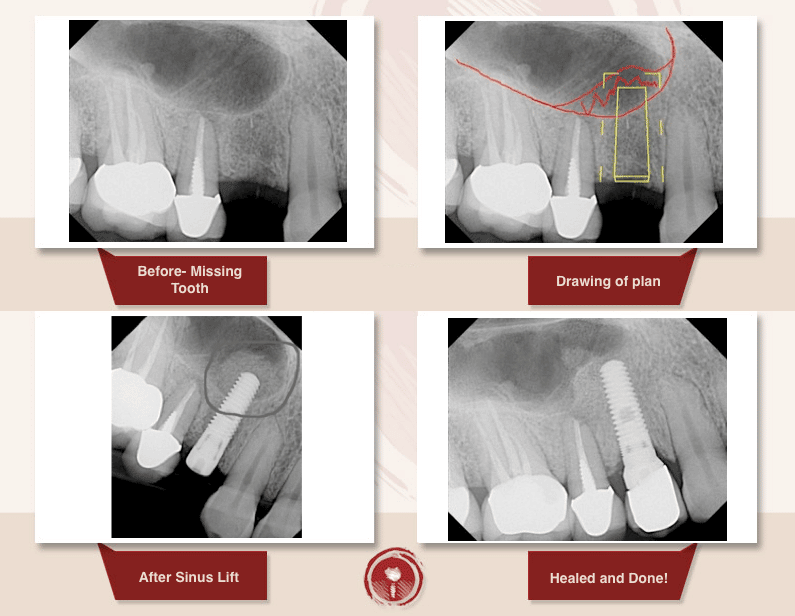

What Is A Sinus Lift And Bone Graft . Dental implants require a certain amount of bone for support, and surgically “lifting” the sinus floor makes more room for new bone to be grafted. People who have limited bone to secure a dental implant may need a sinus lift. sinus lift, or sinus augmentation surgery, adds bone to your upper jaw to make it taller. It takes about 6 months to fully heal. Sinus lift surgery is typically performed when there is not enough bone in the upper jaw, or the sinuses are too close to the jaw, to receive dental implants. sinus lift surgery is a dental procedure used when the existing rear upper jaw (maxilla) bone is insufficient for dental implants. a sinus lift, also known as sinus augmentation or sinus elevation, is a surgical procedure that adds bone to the maxillary. a sinus lift, also known as sinus augmentation, is a surgical procedure that aims to increase the amount of bone in. sinus lift surgery is an oral procedure to extend the upper jawbone into the maxilla sinus cavity with a bone graft. Sinus lifts specifically address bone deficiency in the upper jaw, particularly in the molar and premolar regions affected by the. a sinus lift, sinus augmentation, or sinus floor elevation is a common procedure to prepare someone for dental implants. To reinforce this area, oral surgeons graft harvested or synthetic bone into a space created by lifting the bone matter into the sinus cavity above the mouth.